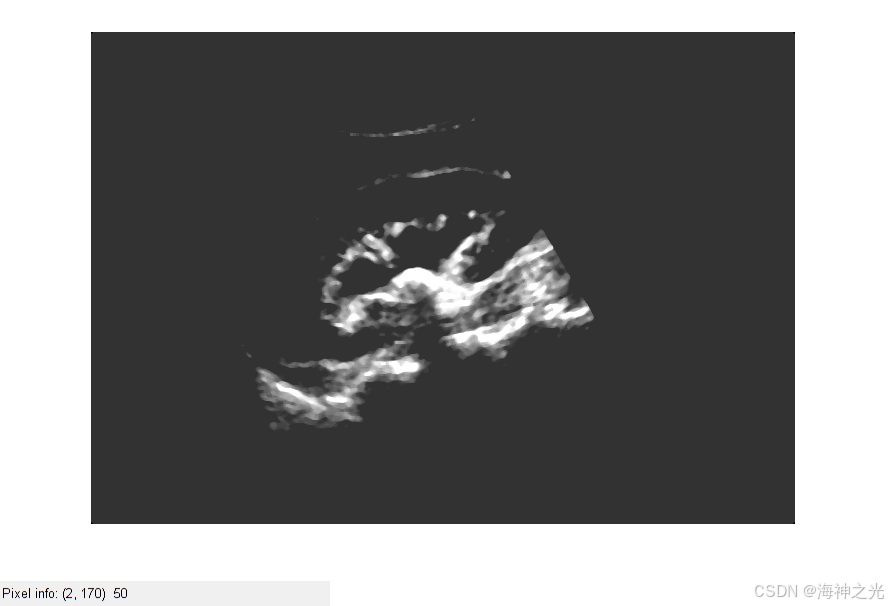

⛄三、运行结果